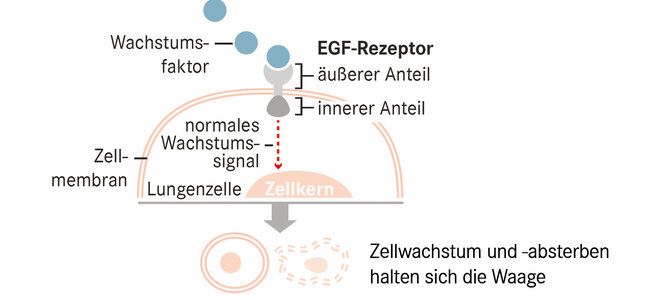

Krebs entsteht, wenn Zellen sich aufgrund genetischer Änderungen ungebremst vermehren. Manchmal lassen sich diese an bestimmten Stellen der DNA festmachen. Dort werden Bausteine ausgetauscht, ganze Abschnitte umverlagert, fusioniert oder vermehrt. Etwas unscharf spricht man dann von „Treibermutationen“, die der Entartung zugrunde liegen. Bei Ärztinnen und Ärzten laufen sie unter ihren Abkürzungen wie ALK oder KRAS.

Am besten untersucht ist dies für EGRF-Mutationen, Ursache für rund 15 Prozent der Adenokarzinome. Osimertinib, der neueste unter mehreren Wirkstoffen gegen diesen Typ, verlängerte die Zeit bis zum Fortschreiten der Krankheit auf 19 Monate; nach 18 Monaten lebten noch 83 Prozent der Patientinnen und Patienten.